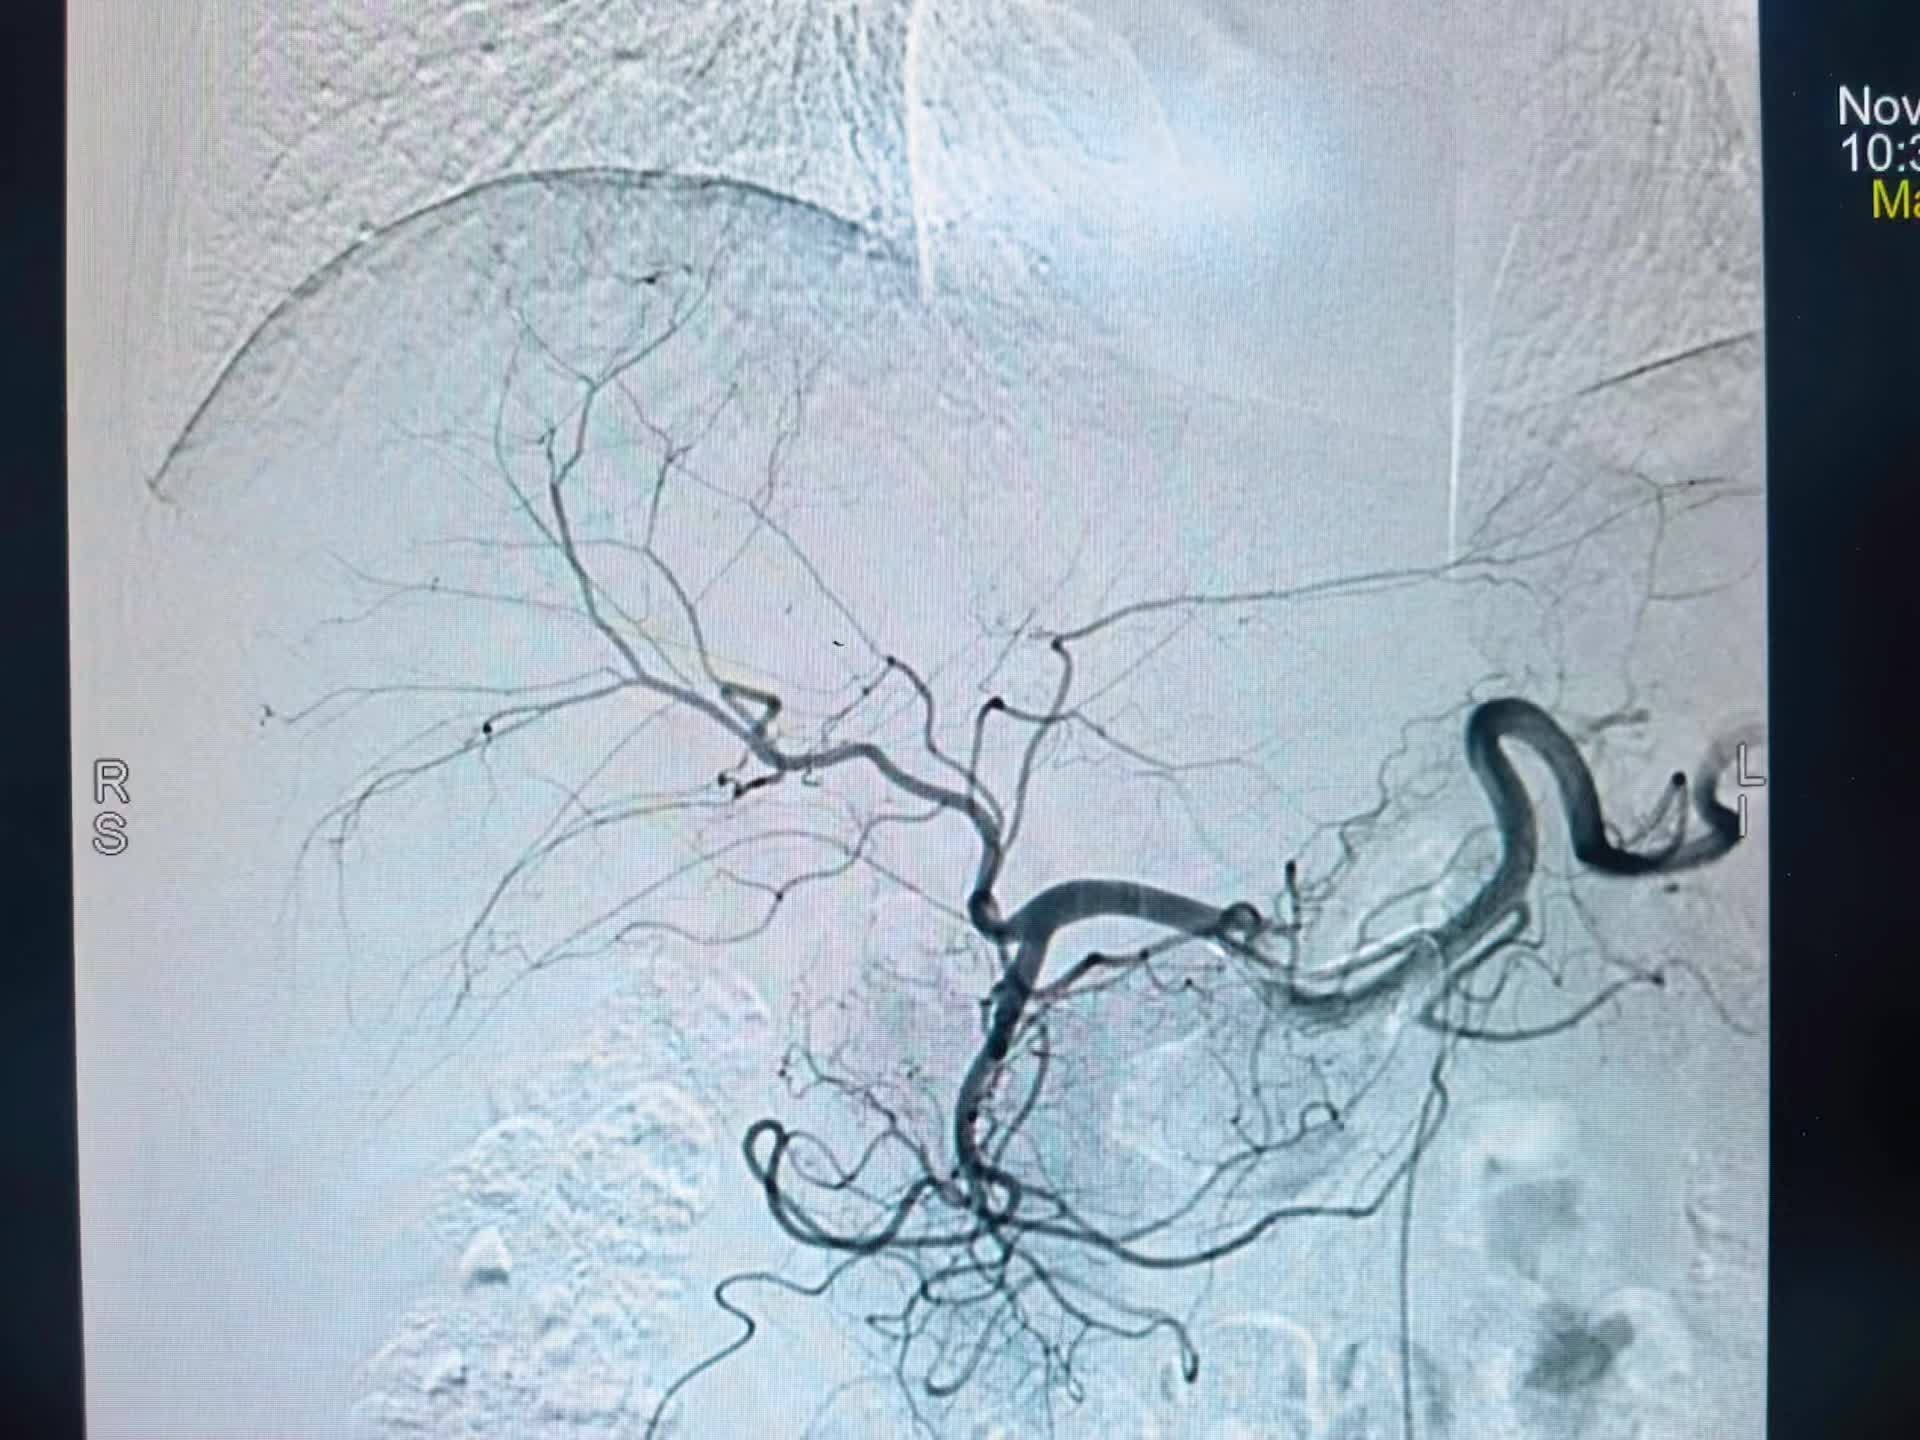

下午第一台糖尿病足三次腔内治疗再次未规律服药再次狭窄闭塞,下肢溃烂发黑,疼痛难忍。再次行球囊扩张术,术后皮温恢复,疼痛减轻。 第二台腮腺癌肝转移,经穿刺活检后证实后。行载药微球的灌注化疗栓塞。